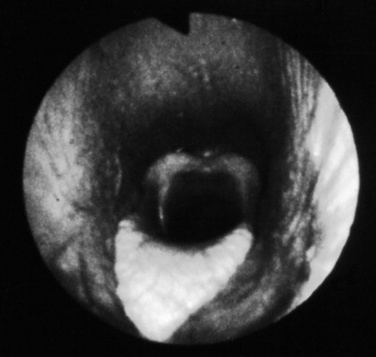

The upper airway can be directly examined with the aid of an endoscope, the only limitations being the size of the patient, the patency of the airway, and the size of the available equipment. Standard flexible fiberoptic endoscopes, available to most practitioners and present now in virtually all referral hospitals, allow direct examination of the nasal passages, ethmoid turbinates, nasal maxillary opening of the sinuses, pharynx, guttural pouch openings, larynx, and cranial trachea (Fig. 31-1). Smaller (8- to 10-mm-diameter) endoscopes can be readily introduced into the equine guttural pouches with the aid of a biopsy instrument, and longer endoscopes (more than 150 cm long with diameters greater than 10 mm) are commonly employed to examine mainstem bronchi and their initial branches in large animals.3 Small brushes, used for collecting exfoliated cells for cytologic study, and a variety of biopsy instruments can be used for sampling the airway. The use of airway endoscopy has evolved to include videoendoscopy of the equine upper airway during treadmill exercise at high speed (12 to 14 m/sec) to evaluate dynamic respiratory function and make objective measurements by use of freeze-frame features.4

Fig. 31-1 Normal equine larynx. The larynx is directly visualized by endoscopy, with both structure and symmetry evaluated.

Courtesy Dr. Corinne Sweeney, University of Pennsylvania, New Bolton Center, Kennett Square, Penn.

Airway abnormalities such as pharyngeal lymphoid hyperplasia, laryngeal hemiplegia, epiglottic entrapment by arytenoepiglottic folds, dorsal displacement of the soft palate, pharyngeal cysts, retropharyngeal masses, and epiglottic deformities are all best diagnosed by endoscopic examination. Guttural pouch diseases and EIPH are also best evaluated using this technique. The degree and nature of airway secretions accumulating in the trachea can be easily assessed using an endoscope, and accumulated secretions may be sampled by aspirating the secretions through small tubing introduced into the trachea via the biopsy channel. Because the endoscope has passed through the nonsterile upper airway, these samples are best suited for cytologic, not microbiogic, evaluation but may be fully compatible with evaluation using newer molecular diagnostic techniques.5-8 Endoscopy has also been used to facilitate removal of foreign bodies from the airway, generally aided by the biopsy instrument.